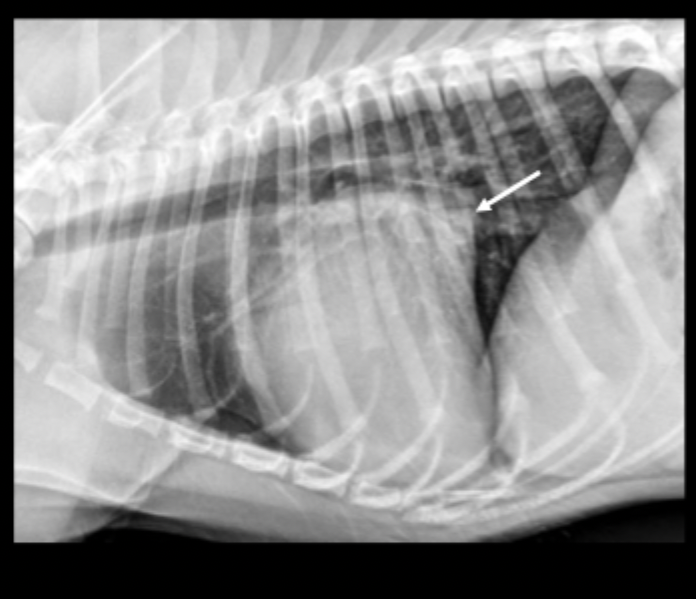

What can be seen on these feline radiographs?

left atrial enlargement

What pulmonary pattern can be seen in this radiograph?

diffuse interstitial pattern

What pattern does feline cardiogenic edema generally present as?

random

patchy

peri-vascular in distribution